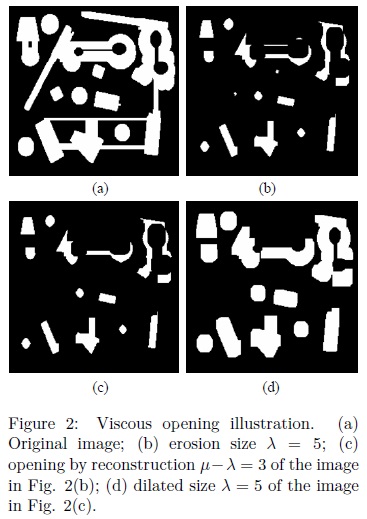

The VASFs will be used to segment some regions of interest. The segmentation process consist in flat the maxima and minima iteratively through the viscous opening and closing. At the end with a threshold is posible to recover the flatened zones under study. Fig. 3 illustrates the performance of Nλn,μ. Notice that, the brain has been completely separated.

Nevertheless, the problem of Eq. 3 is that not always produces the same result and parts of the skull can be obtained in the final segmentation. Due to this situation, the VASFs will be used with the lower leveling1 to improve the final result. Lower leveling transformation is presented below.

An example of this situation can be seen in Fig. 6(g) where the lower leveling is applied considering α = 9. This example is important because it illustrates the approximate size of the remaining components of the skull that should be eliminated. As described before when the VASFs were introduced, once has been considered the dimension of the bone to be removed, the complete skull is supressed by applying the VASFs with λn= 2 and μz= 5 (see Fig. 3). However, due to the volumes processed with the VASFs will contain less information after applying the lower leveling, then the μz parameter can be reduced to 3 instead of 5 with the purpose of reducing the execution time. If λn = 2, the minimum value taken by μz is 3 because of next relation must be fulfilled, λ1 ≤ λ2≤ μz, see section of Viscous Alternating Sequential Filters.